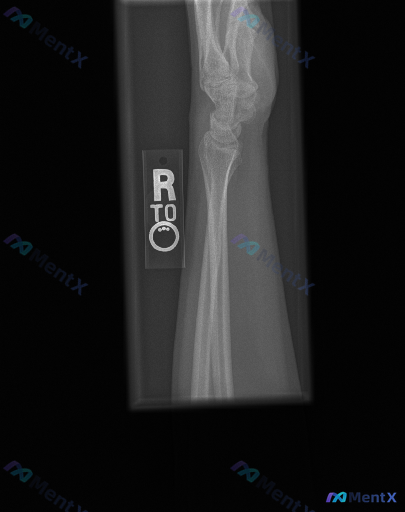

一张右前臂及腕关节侧位X光片,单看影像你会怎么判断?

整理到一份右前臂及腕关节侧位X光片的客观观察资料,先给大家同步一下: 解剖结构评估: - 桡骨远端及尺骨远端可见,骨皮质轮廓尚完整,未见明显的骨折线、皮质中断或骨质塌陷; - 腕骨(舟骨、月骨、头状骨等)序列在侧位投影上大致呈正常对齐关系,未见明显脱位或半脱位; - 桡骨远端关节面与腕骨之间的对线关...